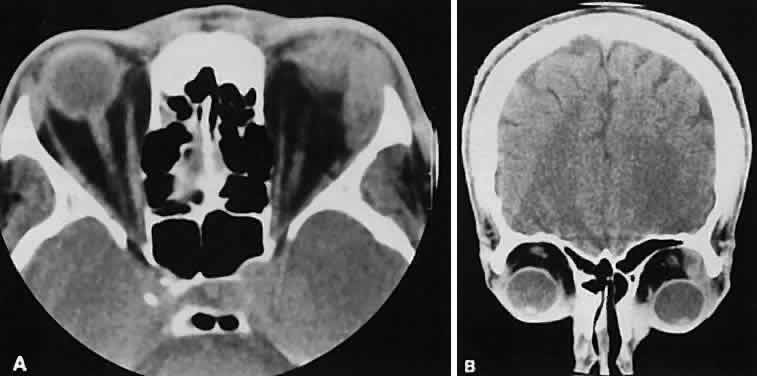

Graves' orbitopathy probably represents the most frequent cause of proptosis and EOM enlargement. The CT findings are fairly stereotyped and typically display various degrees of EOM enlargement (Fig. 7). The inferior rectus muscle usually is affected earliest, followed by the medial rectus, superior rectus, and finally the lateral rectus muscle. Rootman and colleagues13 noted more frequent involvement of the superior rectus/levator and medial rectus muscles than what had been reported previously with Graves' orbitopathy. These muscles can be affected in isolation, with the exception of the lateral rectus. To the best of our knowledge, isolated lateral rectus enlargement has not been reported in Graves' orbitopathy and in our experience usually is associated with a sphenoid wing meningioma.

Fig. 7. Graves' orbitopathy with two variations. Axial (A) and coronal (B) views show symmetric fusiform enlargement of the extraocular muscles with tapered muscle insertions. Note the predominant enlargement of the inferior, medial, and superior rectus muscles with lesser involvement of the lateral rectus muscle, a frequent pattern of enlargement in Graves' orbitopathy. Axial (C) and coronal (D) views of Graves' orbitopathy with expansion of retrobulbar ground substance and relative sparing of the extraocular muscles.

CT evidence of Graves' orbitopathy tends to be bilateral. Approximately 86% of patients with unilateral clinical findings have bilateral CT findings in our experience, which is consistent with the experience of others.42

Morphologically, the EOM belly is enlarged, with a gradual tapering toward and sparing of the tendinous portion of the muscle. Tendon involvement is a typical feature of orbital myositis. Tendon involvement helps to differentiate this lesion from Graves' orbitopathy, although Rootman and Nugent43 have noted a rare patient with Graves' orbitopathy with this finding.